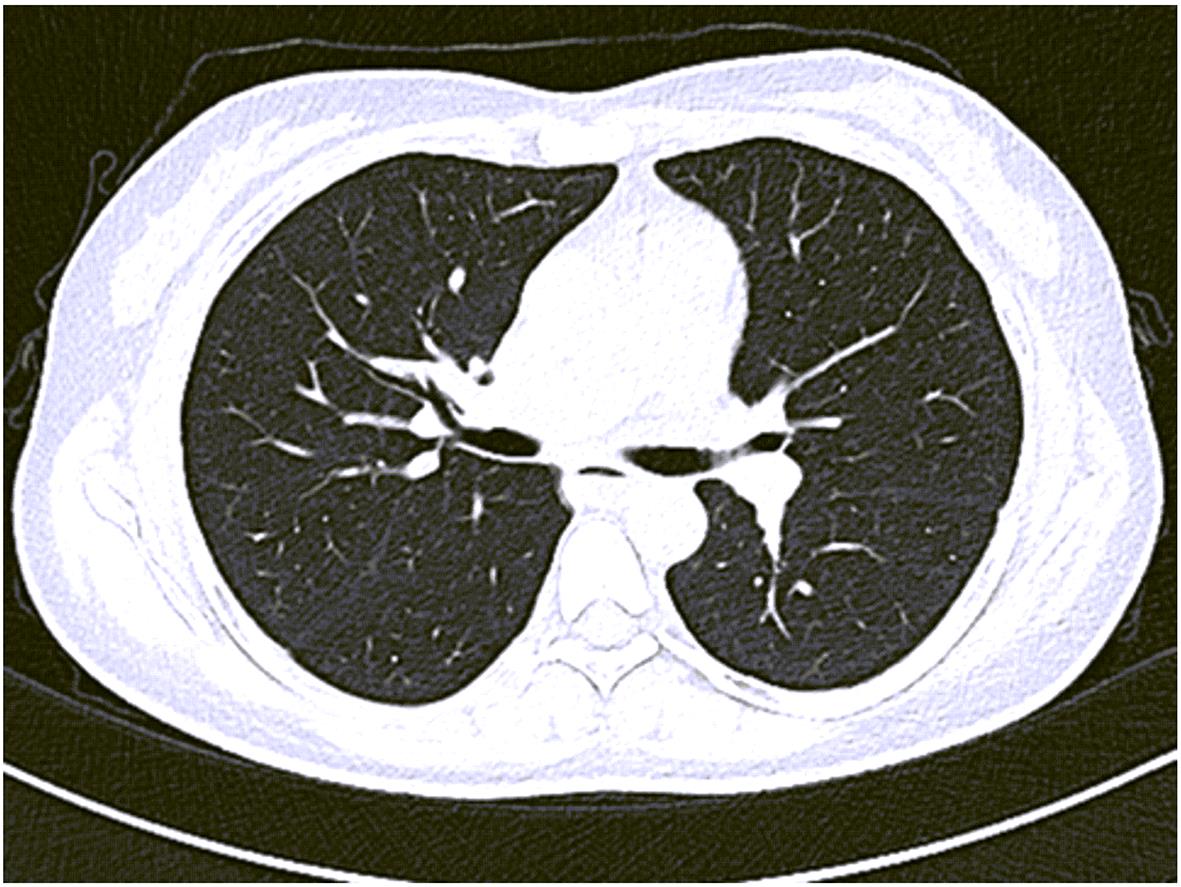

摘要: 本文报道以“肝脾肿大待查”为主诉,经各项检查确诊为B型尼曼-皮克病的案例,并通过文献复习,总结B型尼曼-皮克病肝脏受累的异质性表现,旨在提高疑难罕见肝脏疾病的临床诊治水平。

Abstract: This article reports a case with the chief complaint of “hepatosplenomegaly to be investigated” and a confirmed diagnosis of Niemann-Pick disease type B after various tests, and a literature review was conducted to summarize the heterogeneous manifestations of liver involvement in type B Niemann-Pick disease, in order to improve the clinical management of difficult and rare liver diseases.-